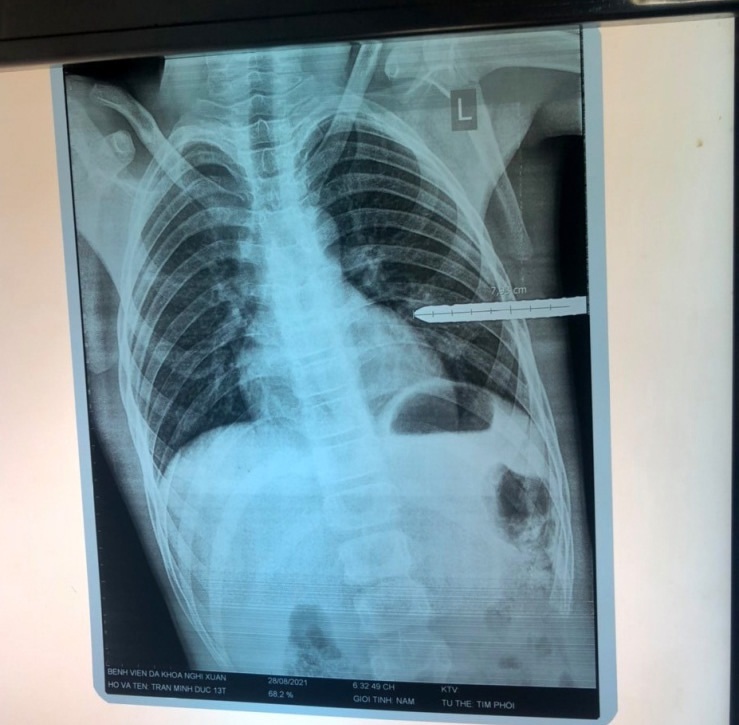

Một bé trai 13 tuổi ở Hà Tĩnh bị thanh sắt đâm xuyên ngực trái, thấu phổi khi chơi đùa, vừa được các bác sĩ cứu sống. Chiều 30.8, thông tin từ Bệnh viện Sản nhi Nghệ An cho biết, các y bác sĩ của bệnh viện vừa cứu sống một bệnh nhi bị thanh sắt dài khoảng 1 m đâm xuyên ngực trái.

Trước đó, chiều 28.8, bệnh nhi T.M.Đ (13 tuổi, ngụ H.Nghi Xuân, Hà Tĩnh) được gia đình đưa đến cấp cứu tại Bệnh viện Sản nhi Nghệ An trong tình trạng đau đớn, khó thở, da niêm mạc nhợt với một thanh sắt phi 10, dài khoảng 1 m đâm xuyên ngực trái.

Sau khi khám và chụp X-quang, bệnh nhi được các bác sĩ Bệnh viện Sản nghi Nghệ An chẩn đoán vết thương thấu ngực, tổn thương nhu mô phổi trái. Kíp mổ thực hiện mở ngực, lấy thanh sắt đang cắm vào phổi trái ra khỏi người bệnh nhi.